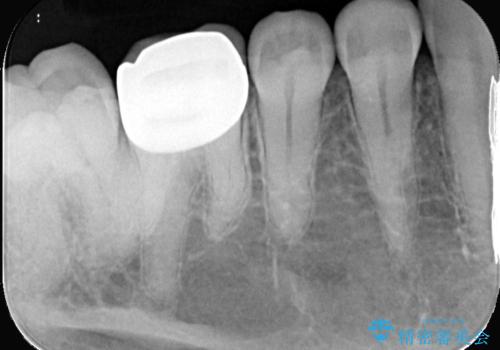

審美性の良いオールセラミッククラウンを選択されました。